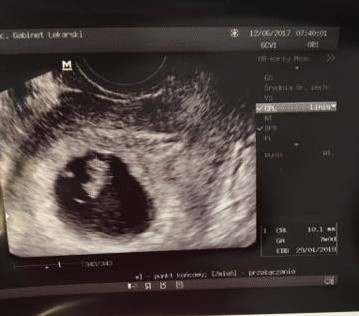

ok już wysyłam oba zdjęcia

19075395_1418836471489181_1634076784_n-crop.jpg

• 19075395_1418836471489181_1634076784_n-crop.jpg

28,1 KB · Wyświetleń: 486

Z tego drugiego to bym nie była pewna. Bo jednak i jasne jest po lewej i z dołu. Ale wiem ze tez się patrzy na to gdzie jest zarodek i wg tego to by wychodziło ze z lewej strony (tam tez mogło by się tworzyć łożysko) co by wskazywało na chłopczyka.

Ja staram się z tych zdjęć patrzeć mniejwiecej bo ładnie widać.